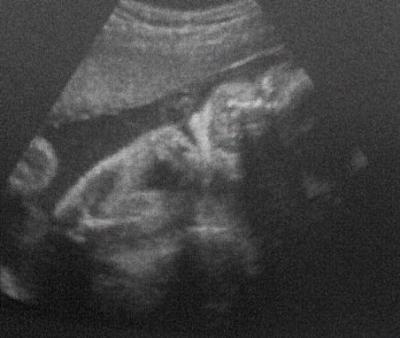

Beim US dann gleich gepost (siehe Bild)

PH-Wert, Plazenta, Fruchtwasser, Muttermund, Gebärmutterhals ist bei 3,8 cm, Baby ist ca 39 cm und wiegt jetzt 1280 gramm also alles total Zeitgerecht und das beste KEINE Wehen.